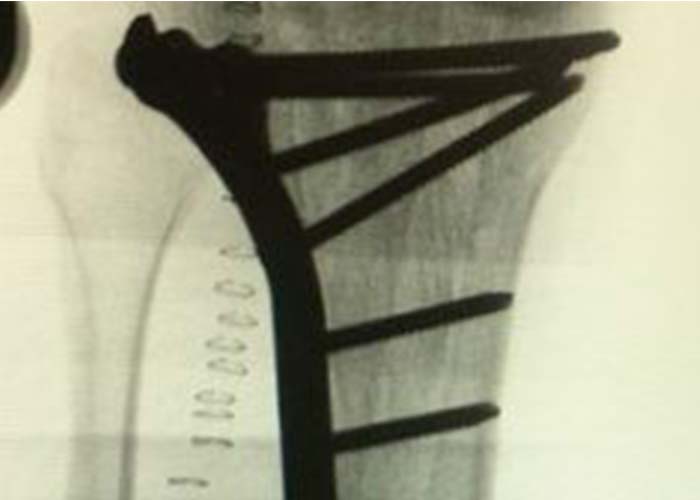

Preoperatorio

Se realiza estudio con pruebas complementarias (radiografías y TAC):

Radiografía anteropostesior y lateral de rodilla derecha en la que se observa una fractura de meseta tibial con apertura y separación longitudinal anterolateral con trazos fracturarios diafisarios.

En TAC se objetiva una fractura conminuta de la meseta tibial con hundimiento del platillo tibial anterolateral con líneas de fractura diafisarias anteriores, mediales y posteriores.

Diagnosticado de fractura meseta tibial según la clasificación de Schatzker, tipo II (combinación de hundimiento y separación) y tipo VI con disociación de la metáfisis y la diáfisis.